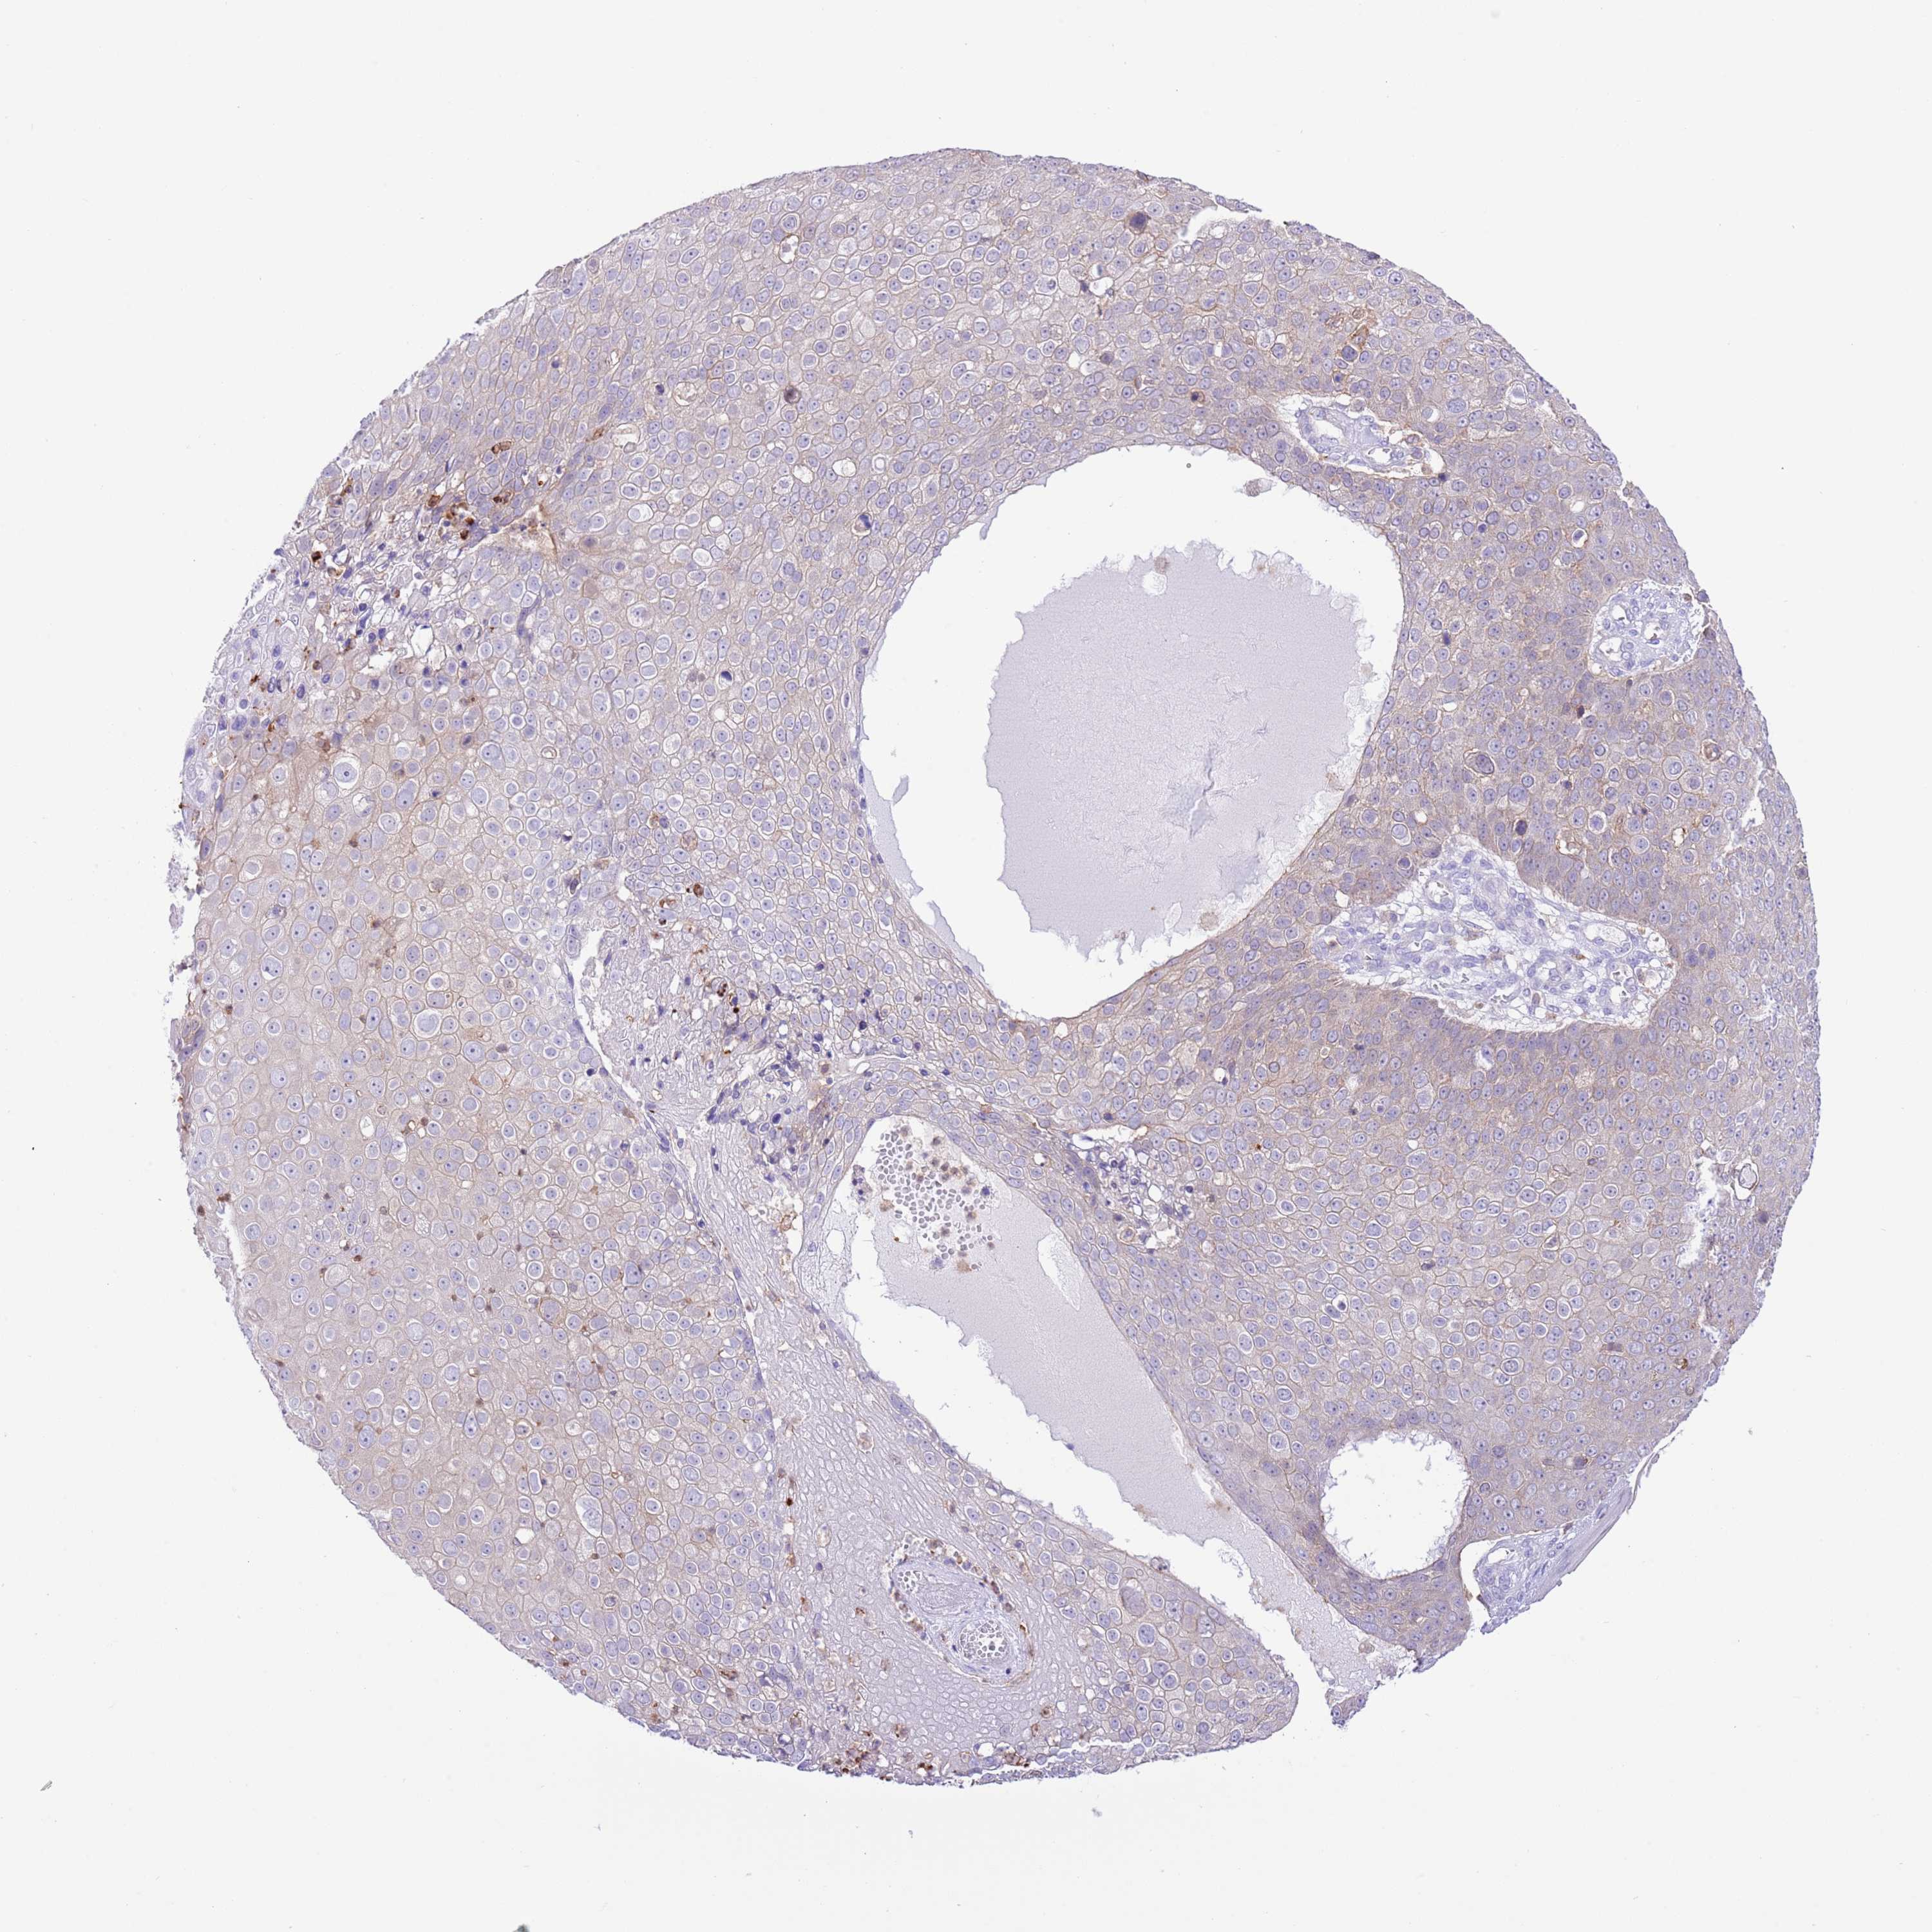

SKIN CANCER - Protein expressioni

A mouse-over function shows sample information and annotation data. Click on an image to view it in a full screen mode. Samples can be filtered based on level of antibody staining by selecting one or several of the following categories: high, medium, low and not detected. The assay and annotation is described here.

Antibody staining in the annotated cell types in the current human tissue is reported as not detected, low, medium, or high, based on conventional immunohistochemistry profiling in selected tissues. This score is based on the combination of the staining intensity and fraction of stained cells.

Each image is clickable and will lead to virtual microscopy that enables deeper exploration of all samples and also displays staining intensity scores, fraction scores and subcellular localization as well as patient and tissue information for each sample.

Antibody HPA048961

Basal cell carcinoma